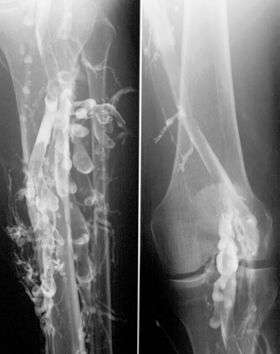

The gold standard for judging imaging methods is contrast venography, which involves injecting a peripheral vein of the affected limb with a contrast agent and taking X-rays, to reveal whether the venous supply has been obstructed. Because of its cost, invasiveness, availability, and other limitations, this test is rarely performed.[3]